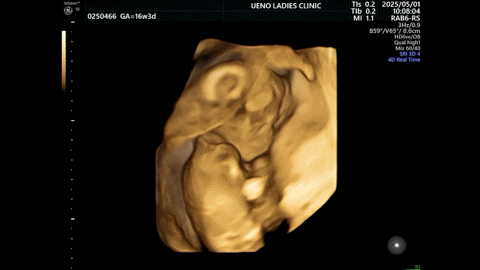

診察では楽しいエコータイム。

今日こそ性別わかるかな?と思っていたが、ずっと横後ろを向いていて、性別は愚か、顔すらわからなかった。